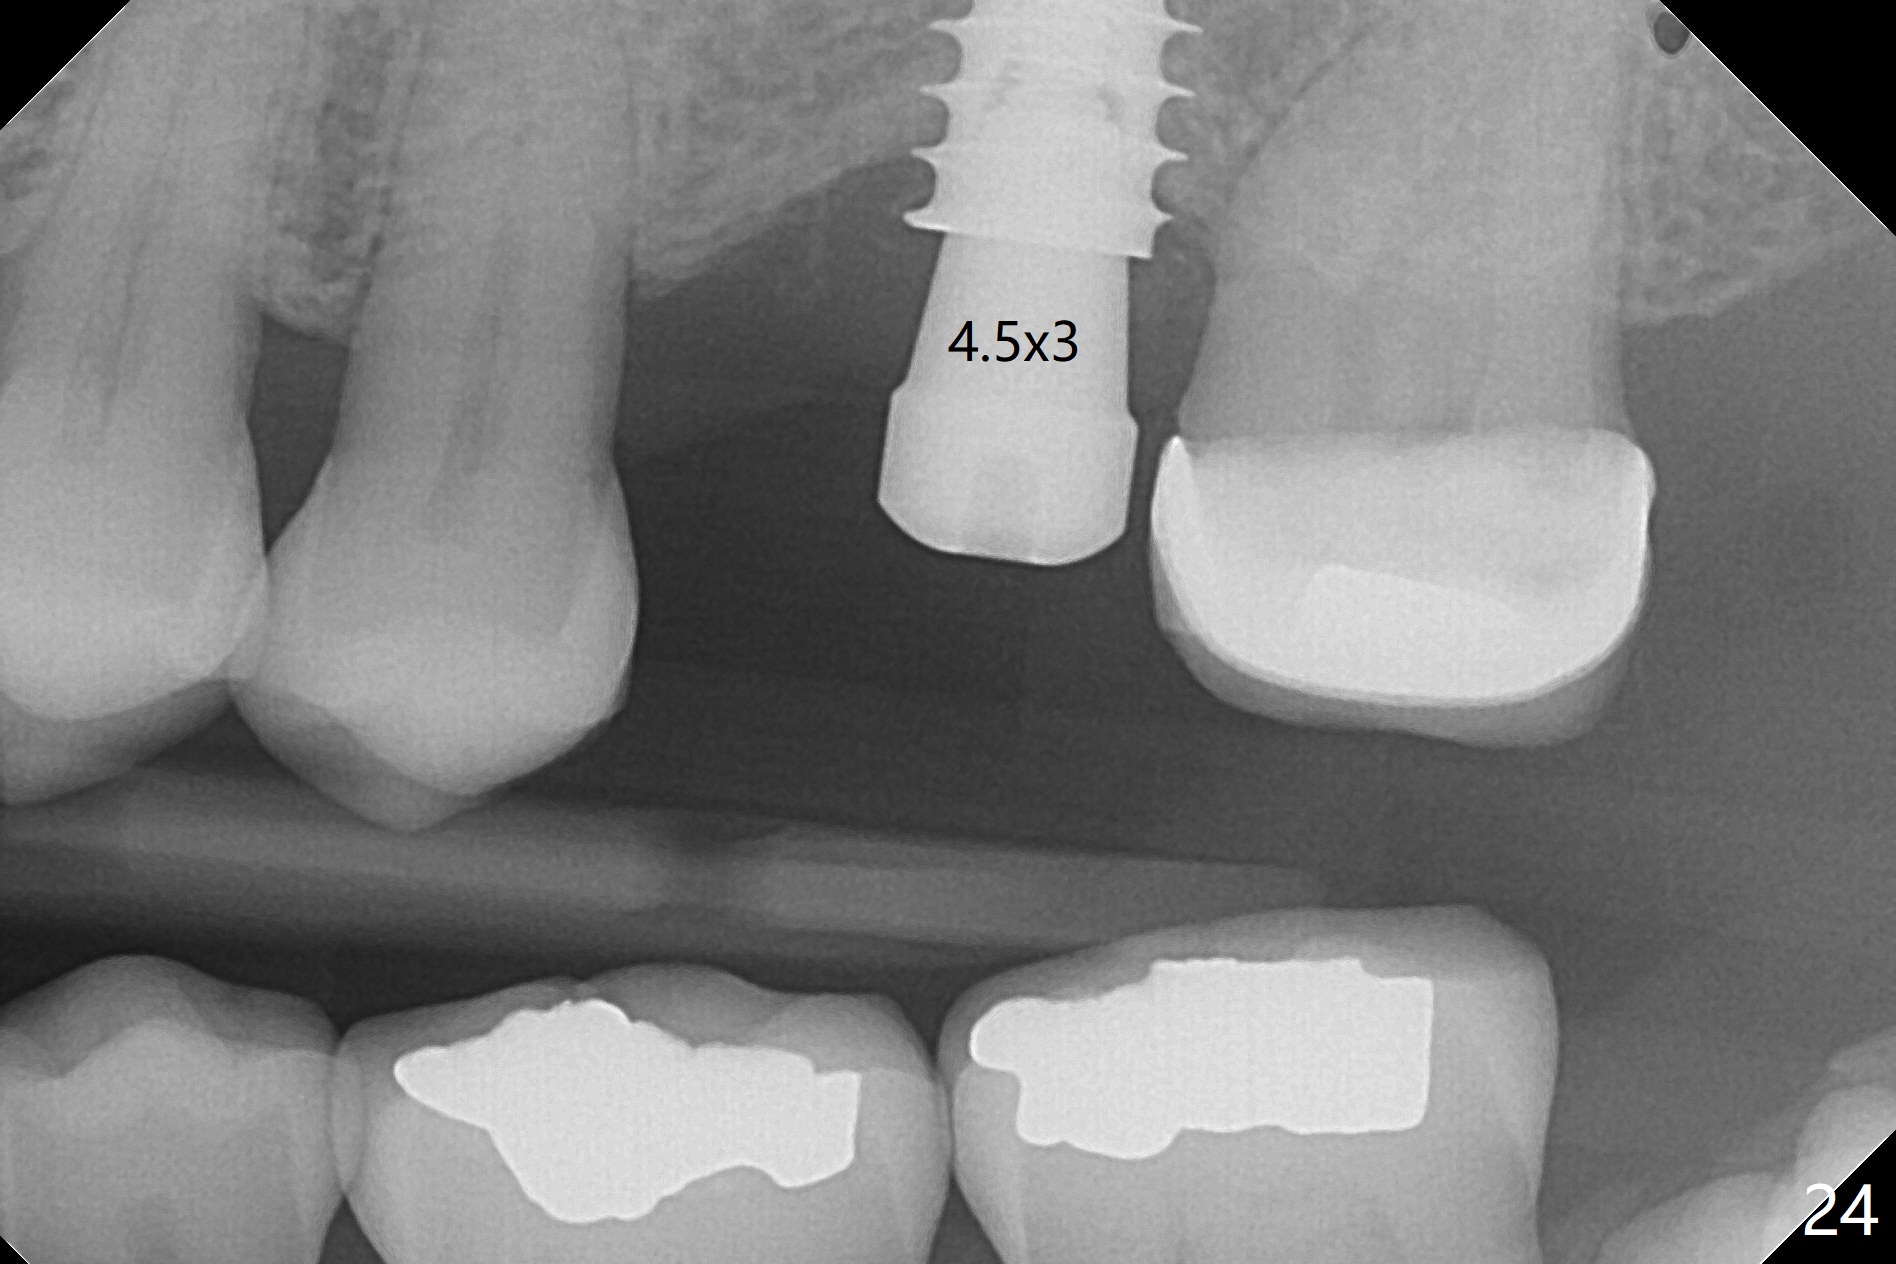

The implant is stable 8 months postop (Fig.15). When a 6x4(3) mm abutment is placed 8.5 months postop, it is distal (Fig.16). The mesiodistal width is 1-2 mm shorter than that at #3, which suggests the mesial shift of the tooth #15. A provisional is fabricated at #14 (Fig.17 P) with supra-occlusion so that there is clearance between the tooth #15 and the opposing one (Fig.18 *). With a separator placed between #14 and 15 (Fig.19), the latter is free to be distalized. Bone volume and density seem to increase 4.5 and 10.5 months post cementation (Fig.20,21, as compared to Fig.15), although the buccal plate remains as concave as shown in Fig.18. One year 5 months post cementation, the patient complains of bad smell from the implant when water pik is being used. It appears that the 1st 2-3 threads are exposed (Fig.22), although the surrounding gingiva remains uninfected. Bone graft is recommended. The site heals without bad smell 7 months post bone graft (2 years 4 months post cementation, Fig.23). The 1st implant thread is found exposed buccal on uncover (regraft?). A small healing abutment is placed because the implant is placed distal (Fig.24). An angled abutment should be tried and #15 crown will be redone. Impression will be taken when the gingiva heals around the provisional crowns.